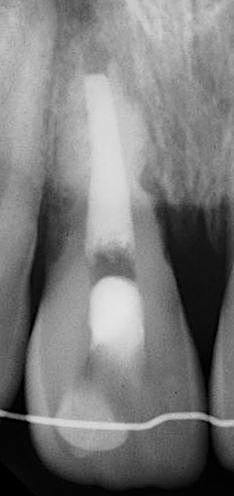

Following the induction of bleeding, a resorbable collagen matrix is placed over the blood clot. Next, a bioceramic material is placed directly over the collagen matrix, a glass ionomer is placed over the bioceramic material, and a final composite or amalgam restoration is placed over the glass ionomer. Once the restoration is complete, a final radiograph is taken (Figure 3 and Figure 4), and the patient is put on 6-month recall for up to 3 years, as dictated by the healing process (Figure 5).25

(3.) Preoperative radiograph of necrotic permanent tooth No. 29.

Figure 3

(4.) Immediate postoperative radiograph after second visit for regenerative endodontic treatment on tooth No. 29.

Figure 4

(5.) Radiograph of tooth No. 29 taken 1 year after regenerative endodontic treatment.

Figure 5